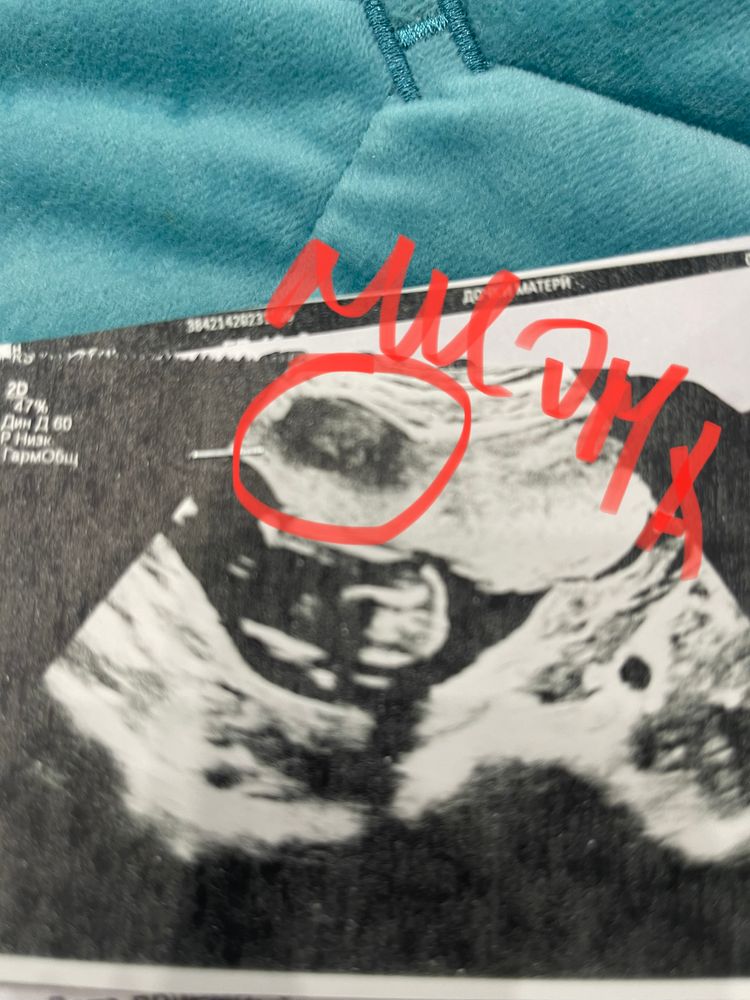

Девочки всем привет. Сходила сегодня на Узи. Не к своему врачу. И она меня прям ошарашила🙈Говорит плацента прикреплена к миоме. На фото пометила кружочком. Она посмотрела все мои старые Узи и говорит тут тоже про это написано, но просто мне это не озвучивали. Сейчас прям страх какой-то. Я у нее пыталась расспросить чем это грозит, она сказала что проблему решать нужно по мере ее поступления. А чего можно ожидать так и не сказала. Сейчас все хорошо. Посмотрели кровотоки все ок. И сказала ходить на Узи каждые две недели для контроля. Скажите кто с таким сталкивался?